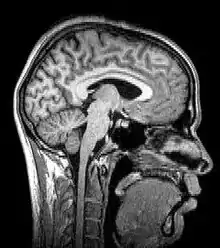

.gif) Para-sagittal MRI of the head in a patient with benign familial macrocephaly | |

Magnetic resonance imaging (MRI) uses magnetic fields and radio waves to produce high quality two- or three-dimensional images of brain structures without the use of ionizing radiation (X-rays) or radioactive tracers.